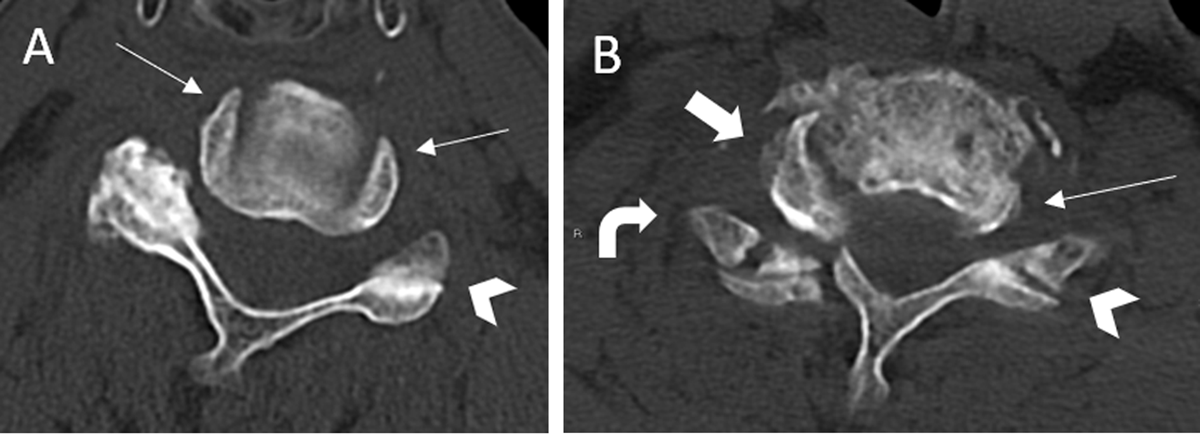

Figure 3

Hamburger bun sign, reverse hamburger bun sign and Naked facet sign.

The “hamburger bun” sign resembles the normal appearance of facet joints on axial CT cervical spine scan of the before-mentioned 77-year-old man (A). Facet joint dislocations upset this relationship and reverse the orientation of the “bun” halves to each other. Hence, the “reverse hamburger bun sign”, also known as “naked facet sign”, represents the appearance on axial CT scan of an exposed facet joint at C6–7 level when it is dislocated (B). These signs are often seen in either unilateral or bilateral facet joint dislocation as a result of flexion-distraction injury—where the inferior articular facet of the upper vertebra projects anterior to the superior articular facet of the inferior vertebra.